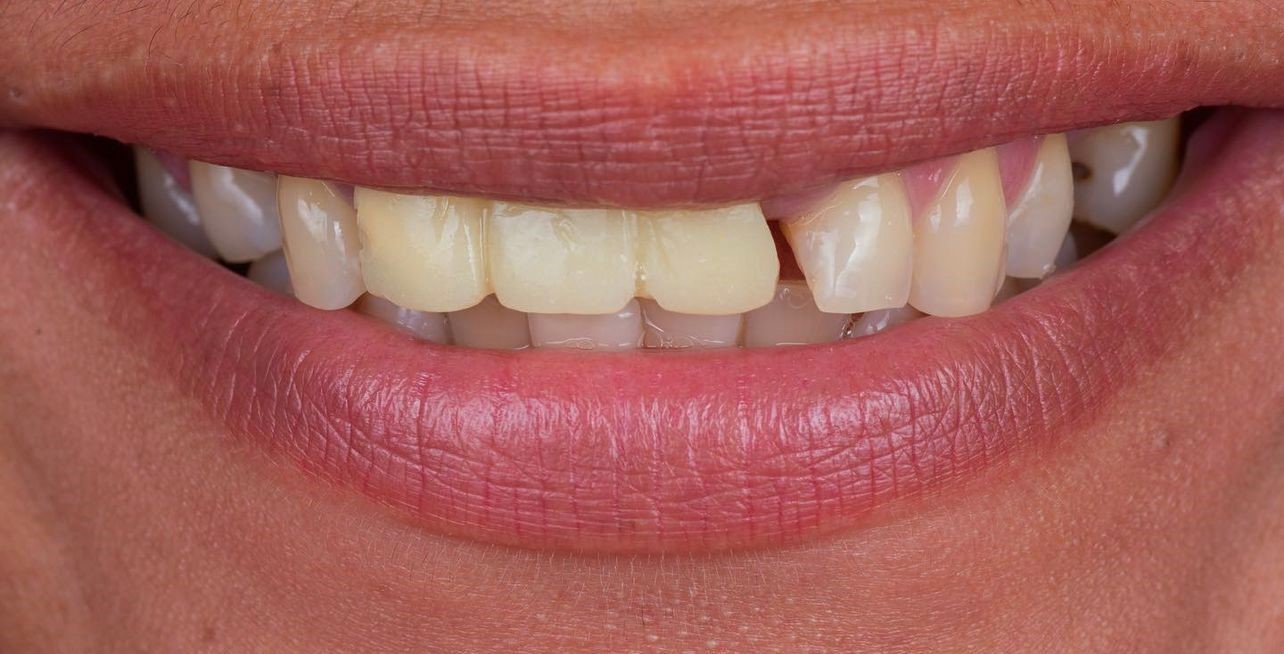

Galeria de Imagenes